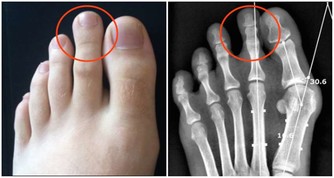

提高思考反應的靈活度、腳部酸痛、

治療風熱感冒、防治腎結石、袪痰、補鈣、

治療風濕病、懷孕止吐、婦科疾病、退燒。